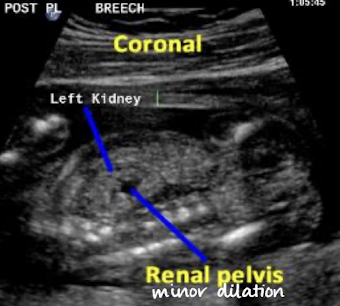

what plane was this taken in?

coronal